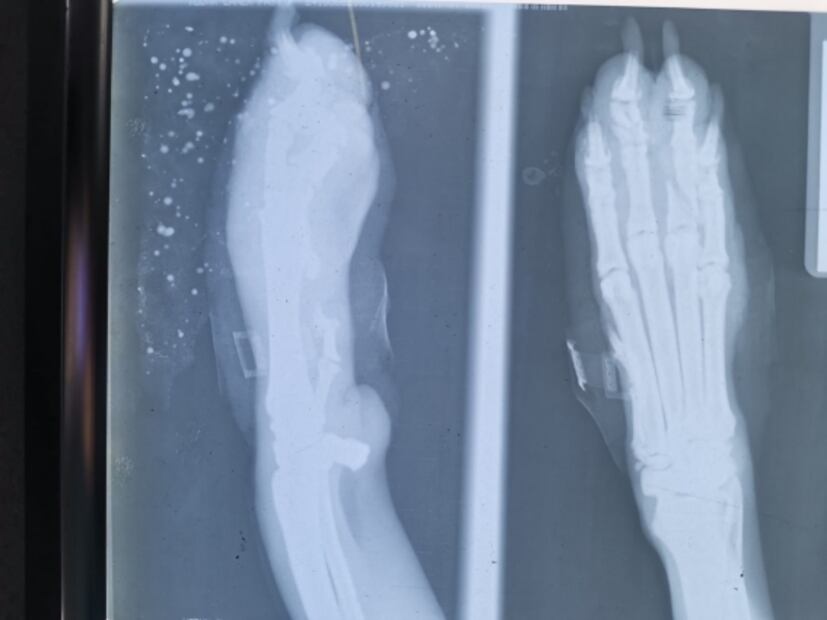

Una de las balas atravesó completamente su extremidad y le fracturó algunos huesos de los dedos, mientras que el otro proyectil se quedó alojado en el vientre, muy cerca de su columna vertebral.

Debido a la gravedad de las heridas, el perro tuvo que ser intervenido de manera inmediata para extraerle la bala.